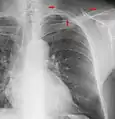

Chest film showing increased opacity in both lungs, indicative of pneumonia